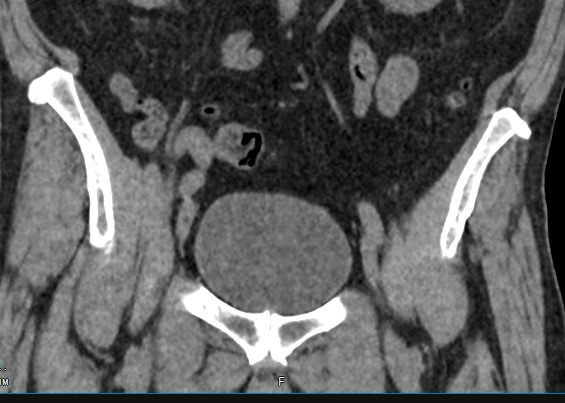

Мультиспиральная компьютерная томография позволяет детально оценить структуру лимфатических узлов, выявить ее неоднородность, определить точные размеры, выявить деформацию контуров, появление инфильтрации окружающих тканей с образованием цепочек, пакетов и конгломератов лимфоузлов.

Мультиспиральная компьютерная томография позволяет оценить структуру лимфатических узлов, обнаружить неоднородность, гиперплазию, деформацию их контуров.

Мультиспиральная компьютерная томография дает возможность визуализировать размеры лимфоузлов, их точную локализацию, взаимодействие с близлежащими органами и окружающими тканями, образование спаянных между собой инфильтратов лимфоузлов, выявить прорастание в окружающие ткани.

При проведении компьютерной томографии можно диагностировать следующие заболевания лимфатических узлов:

- Метастазы в лимфоузлах (поражение лимфатических узлов таза и подвздошных областей на фоне опухолей органов малого таза, брюшной полости;